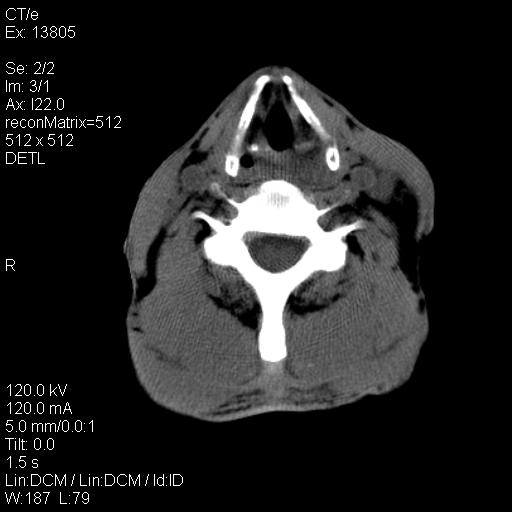

上腹部疼痛一月,呕吐10天,发现左侧颈部包快10天 胸部cr片未见明显异常。

左侧胸锁乳突肌下方、颈血管旁低密度肿块影,肿块密度尚均匀,边缘大部分清楚,邻近组织稍受压移位。考虑颈部神经鞘瘤可能性大。